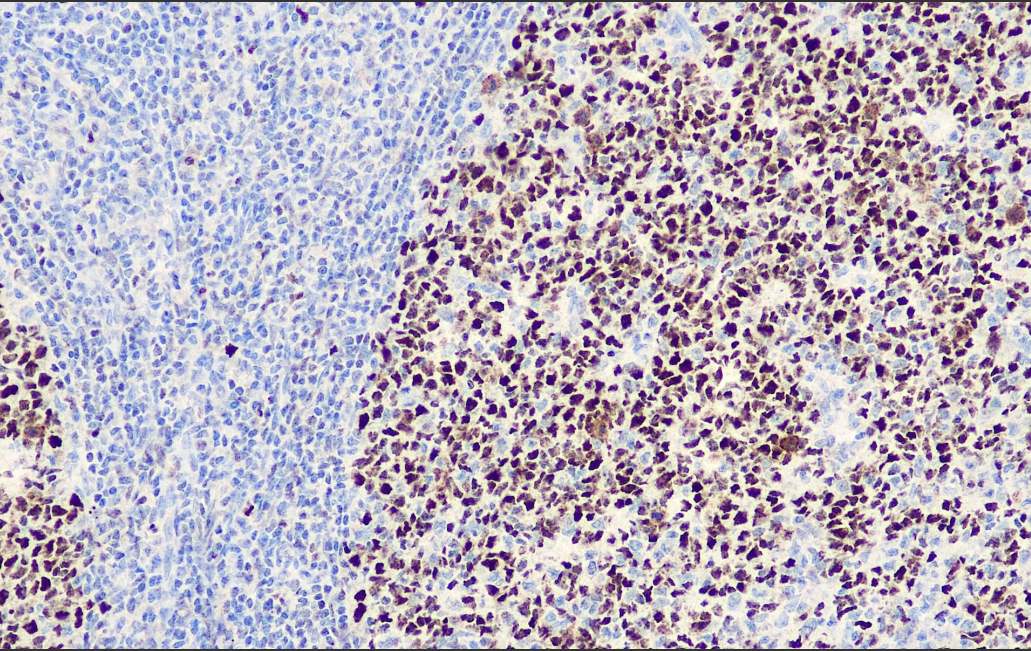

阳性对照: 扁桃体

Bcl-6,又名LAZ-3,是POZ/锌指(POK)家族的一个成员,其含有一个N-末端POZ结构域和6个C-末端锌指基序。Bcl-6是一个在淋巴细胞、肌细胞、雄性生殖细胞和角质化细胞生存和分化中起重要作用的转录调节因子。主要表达于正常生发中心B细胞和相关的淋巴瘤。在滤泡性淋巴瘤、弥漫性大B细胞淋巴瘤、Burkitt淋巴瘤中有不同水平Bcl-6的表达。

Bcl-6抗体试剂可与Bcl-6分子抗原特异性结合,含Bcl-6抗体试剂的免疫组化试剂盒适用于滤泡性淋巴瘤、弥漫性大B细胞淋巴瘤、Burkitt's淋巴瘤以及结节性淋巴细胞为主的何杰金氏淋巴瘤的精准诊断。